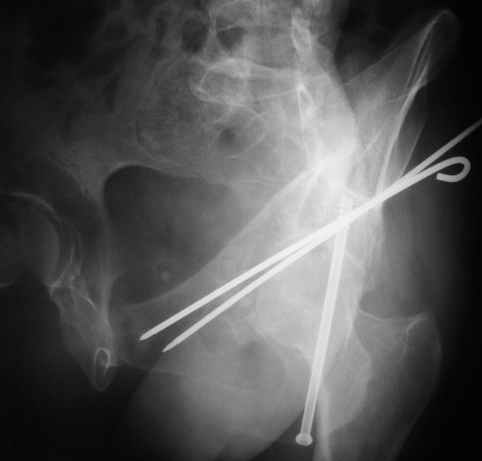

Не дождавшись советов, в понедельник прооперировал больного, заняло времени..., но все сделал в один этап: сначала фиксировал ипсилатеральный перелом бедра и шейки реконструктивным гвоздем Smith&Nephews, потом из расширенного илеофеморального доступа фиксировал перелом крыла подвздошной кости тягловым винтом, нейтрализующей пластиной заднюю колонну, и тягловыми винтами 3,5 мм переднюю колонну.

К сожалению, набора для ретроградного или антеградного реконструктивного штифтования в операционной нет, поэтому доставка заняла н-ное время. Вопрос, который возник у меня- по поводу оптимальной тактики хирургии: вся фиксация в один этап из расширенного доступа или последовательно сначала бедро и позже реконструкция впадины, комбинированный доступ к впадине отдельно к передней и задней колоннам или из расширенного илеофеморального одного доступа. Все-таки решил остановиться на одноэтапном подходе и спустя 5 дней (как раз и наборы привезли) из расширенного илеофеморального доступа сначала фиксировал реконструктивным штифтом Smith&Nephews бедро и

шейку (благо перелом шейки 2 типа -относительно стабильный) затем фрагмент крыла подвздошной кости Lag screw, далее пластина на заднюю колонну и винты в переднюю колонну.(с размерами и направлением винтов ошибка вышла:-((, но интраоперационно у меня была полная уверенность , что винты *ушли* в лонную кость).

Еще раз спасибо за комментарии и готовность помочь с имплантами. Постоп картинки в приложении,